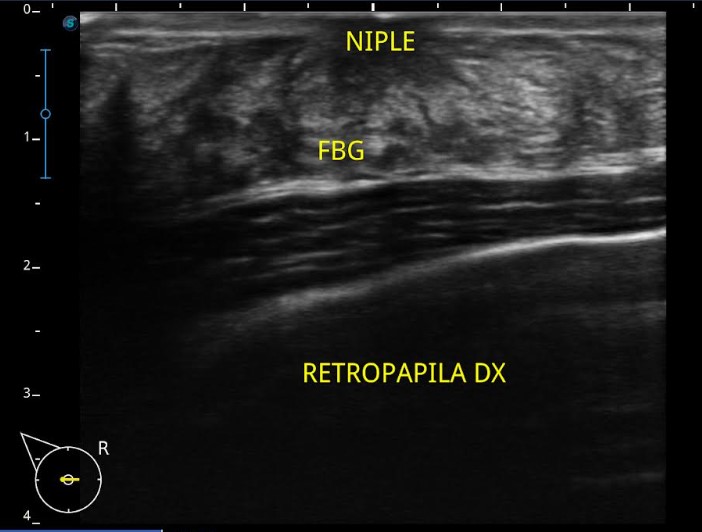

The diagnosis of gynecomastia can be made using mammography or ultrasound examination. On mammography, a high-density lesion in the retroareola can be found in the form of nodular, dendritic or diffuse glandular. While the ultrasound picture of gynecomastia cases can be found in the form of triangular hypoechoic lesions in the retroareola surrounded by fibrous breast tissue.

Image 1. A male 18 y.o with right breast enlargement since 6 months ago, ultrasound examination finding shows fibroglandular tissue in the retropapila mammae dextra.